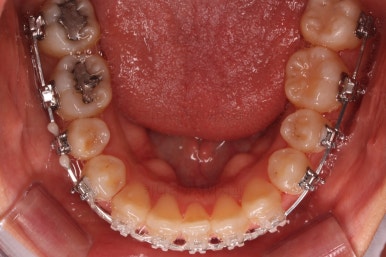

아랫니는 최대한 추가 발치 없이 후방의 송곳니를 당겨와서 앞니 역할을 하게 했습니다.(총 4개 앞니처럼)

부분적으로 장치 셋팅을 다시 해줬고요.

밀고 당기기를 위해서 미니스크류를 셋팅했고요.

교합과 중앙선 및 디테일을 맞춰 나갑니다.

중앙선, 교합, 앞니 맞물림 등 모든 것이 좋아졌네요.

교합, 정중선 모두 좋아졌고요.

웃을 때 한 쪽으로 쏠려있던 중앙도 개선되어 예뻐졌고, 치아 높낮이도 조절하여 웃을 때 보이는 앞니의 길이도 매우 예븐 정도로 조절이 되었습니다.